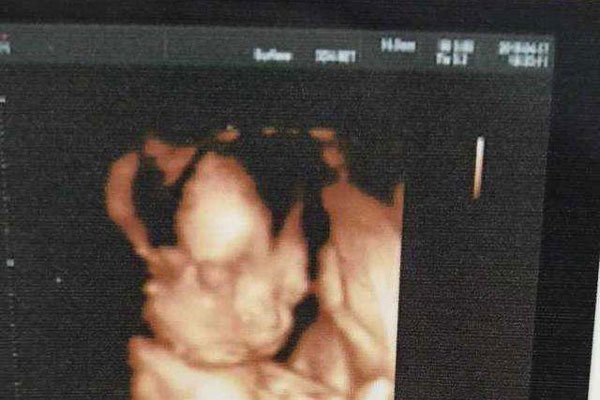

怀男孩的征兆是说:酸儿辣女、孕肚是尖尖的、妊娠线又细又长、孕妇鼻子变大、肚脐眼外凸、一般比预产期早出生的是男孩,延后的则是女孩、肚皮上突然出现好多的毛发、测试清宫表的时候、皮肤变的非常差等等,这就是说明了可以有男孩子,至于真假也不是我们就可以知道!